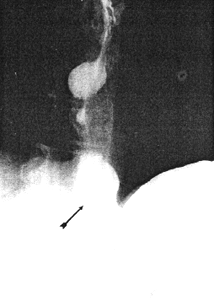

Case 32.1. E.B., 5 weeks old female infant, was admitted with a history of vomiting after feeds and recurrent bilateral pneumonia. Radiographic examination showed a severe, constant narrowing of the pyloric sphincteric cylinder, with a "string sign" typical of IHPS (Fig. 32.1A). The gastro-oesophageal junction was patulous with free and persistent gastro-oesophageal reflux, diagnosed radiographically as a sliding hiatus hernia (Fig. 32.1B). Some aspiration of refluxed barium occurred. At operation the next day a pyloric "olive" measuring approximately 2.3 cm x 0.8 cm, typical of IHPS, was found. Ramstedt pyloromyotomy was done; post-operatively vomiting stopped and the patient made an uneventful recovery.

| Fig. 32.1 A,B. Case E.B. A Constant narrowing of pyloric sphincteric cylinder with string sign (arrows), typical of idiopathic hypertrophic pyloric stenosis. B Patulous gastro-oesophageal junction with free reflux (arrow) |